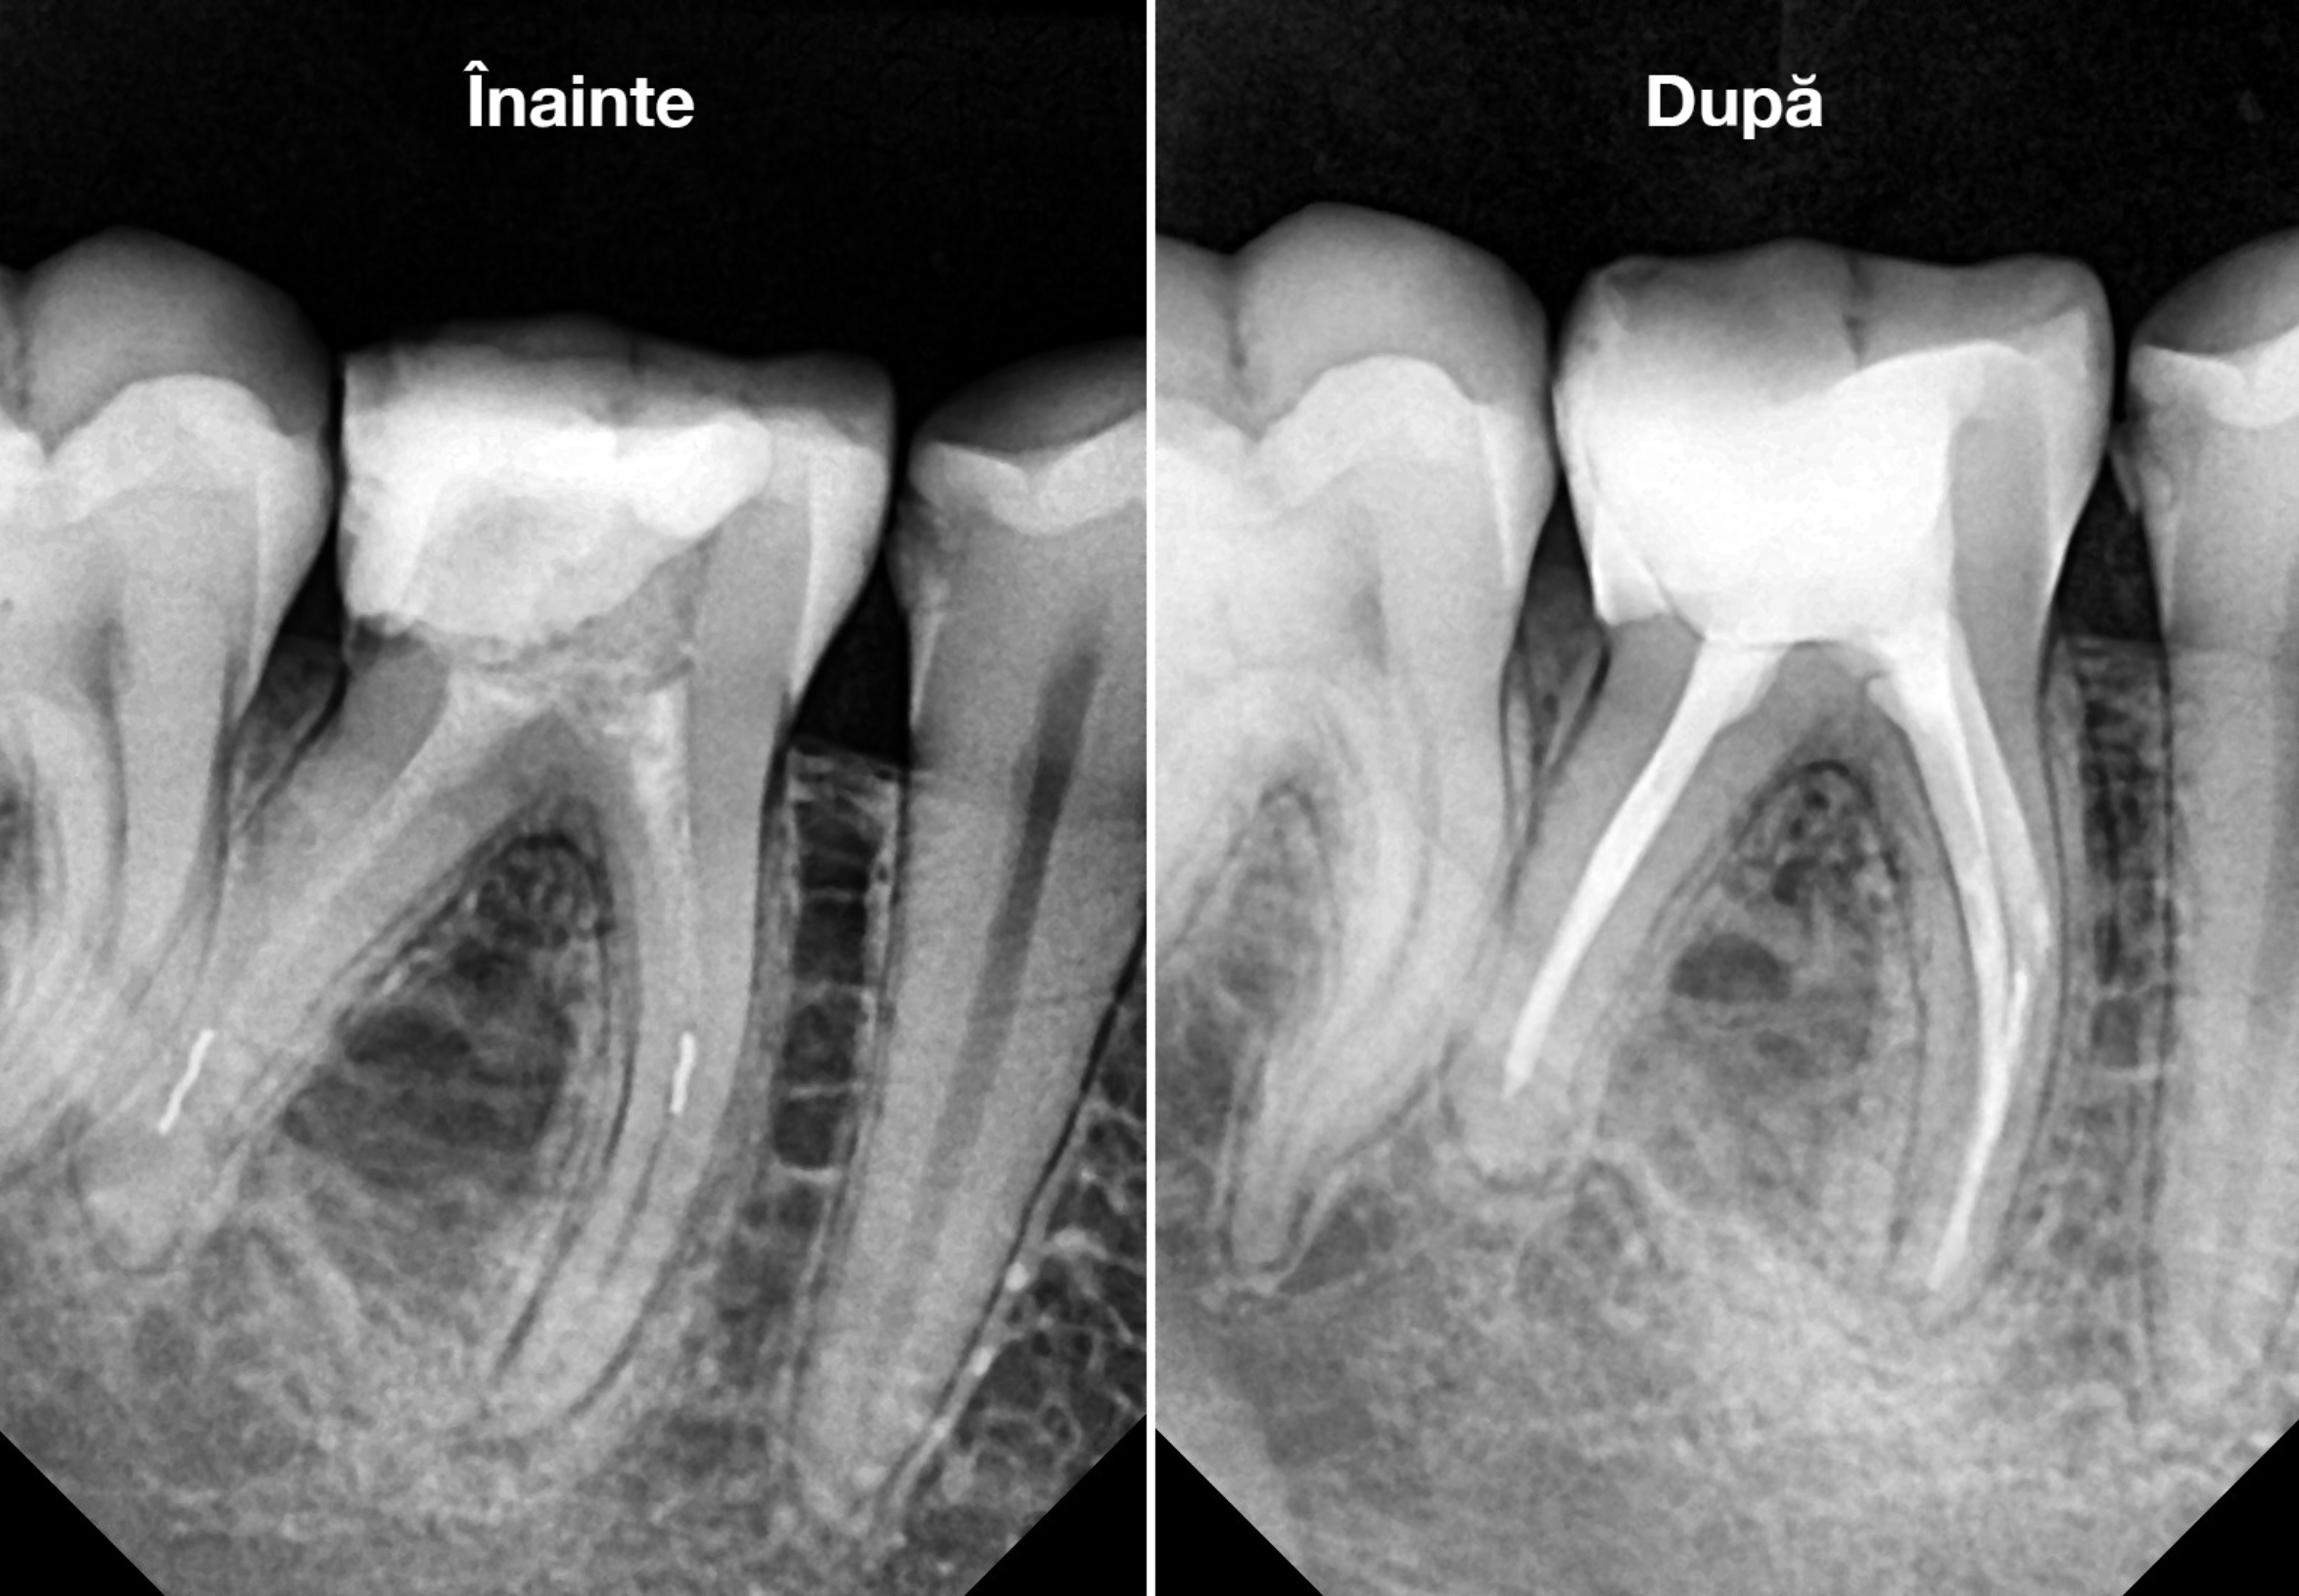

Cazul descris este al unui pacient care s-a prezentat la noi in clinică cu plângeri referitoare la dintele 46. Acest dinte a fost tratat anterior, în urma intervenţiei a rămas câte un fragment de ac în fiecare radacina.

Pacientul prezenta simptome de parodontită apicală, manifestate prin dureri și disconfort la masticatie. Parodontita apicală cronică reprezintă o inflamație persistentă la nivelul țesuturilor de la vârful rădăcinii dintelui, rezultată din infecția bacteriană al canalului radicular. După evaluarea clinică și radiografică, s-a constatat că fragmentele de ac separate accidental împiedicau vindecarea completă a infecției și a inflamației. Tratamentul endodontic inițial nu a fost suficient pentru a remedia problema.

Astfel, s-a decis refacerea tratamentului iniţial, fapt ce a implicat instrumentarea canalelor radiculare și curățarea lor adecvată, realizând bypass-ul (ocolirea) fragmentului din rădăcina mezială şi înlăturarea celui din rădăcina distală. După finalizarea procedurilor, pacientul a raportat dispariția simptomatologiei și ameliorarea disconfortului la masticatie.

În concluzie, cazul a fost abordat cu succes prin efectuarea unui tratament endodontic și prin managementul al fragmentelor de ace ce împiedicau instrumentarea adecvată a spaţiului endodontic. Aceste proceduri au avut ca rezultat vindecarea patologiei și ameliorarea simptomatologiei, restabilind sănătatea și funcționalitatea dintelui.